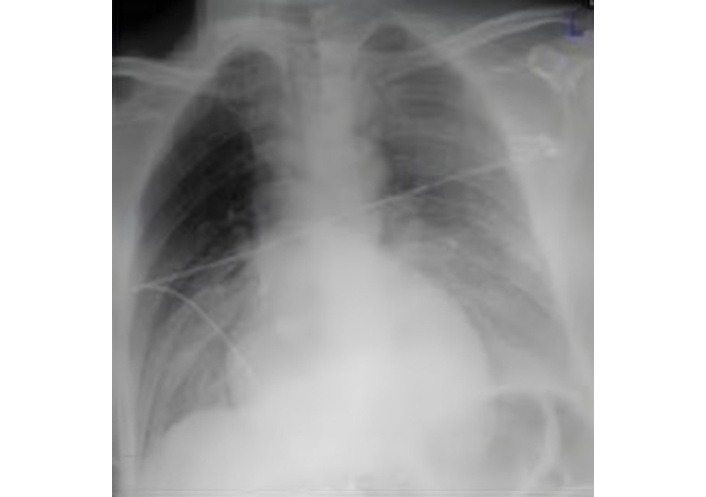

Cardiac enlargement and fractured left 2nd, 3rd, and 5th ribs were the important findings of chest X-ray (CXR) at first admission (Figure 2). Transthoracic echocardiography (TTE) and thoracic computed tomography (CT) confirmed a massive pericardial effusion (Figure 3). Cardiac valvular functions were normal. All of this indicated significant cardiac injury and ongoing cardiac tamponade. The diagnosis was confirmed once the pericardial cavity was accessed.

A TTE evaluation performed three months later did not report the mass seen on CXR as a possible pseudoaneurysm (Figure 4). The mass on the left side became more prominent on CXR (Figure 5), nineteen months later. A thoracic CT scan revealed a giant pseudoaneurysm on the posterior wall of LV which was 10 cm × 7 cm in size (Figure 6). The patient was urgently transferred to our center for definitive management, where a coronary angiography (CA) was performed. CA showed normal coronary anatomy (Figures 7 and 8), but left ventriculography confirmed the diagnosis: leakage of contrast medium into the pseudoaneurysm sac was clearly observed (Figures 9 and 10).

In a retrospective analysis of this case, the mass on the left side, seen on a CXR taken three months later, was not detected by TTE (Figure 4). Although TTEs are often the first test performed due to their widespread availability and routine use in the initial evaluation of patients, they have low sensitivity in detecting pseudoaneurysms. It is a fact that the more posterior the aneurysm, the more difficult its detection by TTE [7]. In this case, the absence of symptoms and the lack of a prior myocardial infarction were also significant factors in not raising sufficient suspicion for diagnosis. We believe that the severe pericardial adhesions associated with the initial surgery prevented the rapid progression and rupture of the pseudoaneurysm.